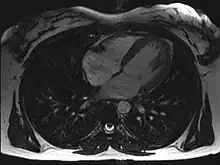

Magnetic resonance imaging (MRI)

Magnetic resonance imaging visualizes the heart by detecting hydrogen atoms using superconducting magnets, particularly those attached to water and fat molecules.[9] These hydrogen atoms possess a property known as nuclear spin. Although the direction of this spin is usually random, the spin can be aligned using a powerful magnetic field.[9] Faint electromagnetic signals are emitted by these hydrogen atoms when their alignment is temporarily disturbed which can be detected and used to create an image of the heart.[10]

Cardiovascular magnetic resonance (MR) technology is able to measure the size, shape, function, and tissue characteristics of the heart in a single session.[11] It is also commonly used to determine ventricular function and for the evaluation of structural heart disease.[12] It is more reproducible than echocardiography with less inter-observer variability, allowing for more precise reference ranges to better distinguish health from disease.[11] Additionally, MR lacks ionizing radiation and does not have any known long-term effects, making it safe for repeated imaging.[13]

Additional benefits from cardiac MRI include the ability to detect scar within the heart using late gadolinium enhancement, and identify other abnormalities of the heart muscle itself such as infiltration with iron or amyloid protein.[11] Disadvantages of MRI include lengthy protocols and the potential for claustrophobia. Furthermore, an MRI scan cannot be performed in some people who have metallic implants such as some types of pacemakers, defibrillators, although many modern pacemakers are safe for use within an MRI scanner.[14] Other metal structures such as artificial valves and coronary stents are generally not problematic. However, MR is less widely available and may be more difficult for patients to tolerate than other noninvasive modalities, requiring physician monitoring for complex cases.[13]

Recent development in deep learning and convolutional neural network techniques have made it possible to analyze and quantify some aspects of cardiac MRI automatically.[15] The use of cardiac MRI is projected to increase through greater availability of scanners and more widespread knowledge about its clinical application.